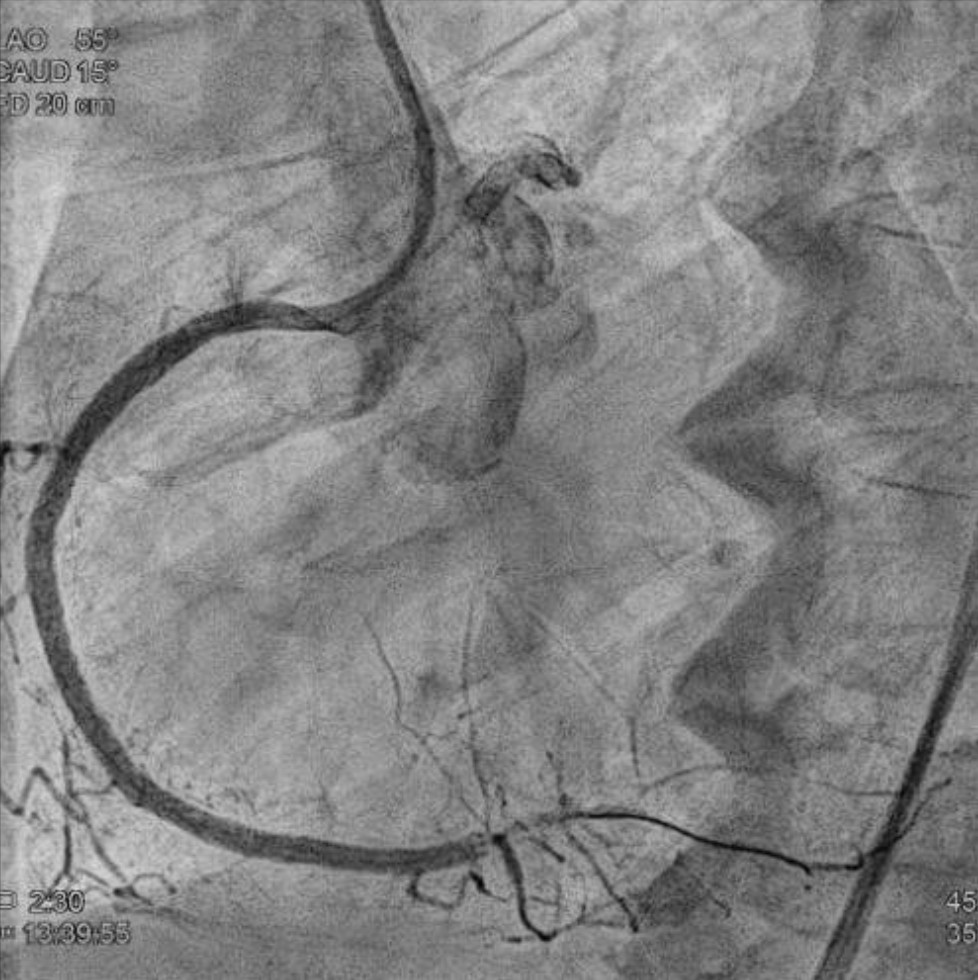

We advanced a 6F JR 4.0 SH 100cm guiding catheter and crossed the RCA ostial lesion using a Fielder FC guidewire. Pre-dilatation was performed with Ryurei 1.5¡¿15mm balloon. IVUS was then performed, revealing a patent stent in the proximal to mid RCA. However, the ostial RCA stent was under-expanded, with smooth muscle compressing the stent from outside. Balloon pre-dilatation was carried out using an NC Euphora 4.0¡¿12mm balloon, inflated up to 22 bar. However, the lesion was resistant and could not be fully dilated. We then applied a 4.0mm intravascular lithotripsy balloon with a total of 100 shocks delivered. But the effect was still minimal. The IVUS showed limited additional plaque fracture or vessel expansion. We tried NC Sapphire II 4.5¡¿8 mm balloon inflation to 18 bar, but it was ineffective due to balloon slippage. The angiogram after oversized NC dilation showed residual stenosis of 59%. We then selected a Wolverine Cutting Balloon 4.0¡¿10 mm and initiated dilation to 6 bar, which resulted in easy slippage again. Subsequent oversized dilations were performed at 18 bar, after which the lesion was successfully dilated. Using a Runthrough Floppy guidewire with the floating wire technique, a drug-eluting stent Biofreedom Ultra 4.0¡¿14 mm was deployed in the ostial RCA ISR. We inflated at 14 bar for 14 seconds, repeated twice. Final post-dilatation was performed with an Accuforce 4.0¡¿15mm balloon. The final IVUS showed good stent placement and expansion. We closed the procedure.